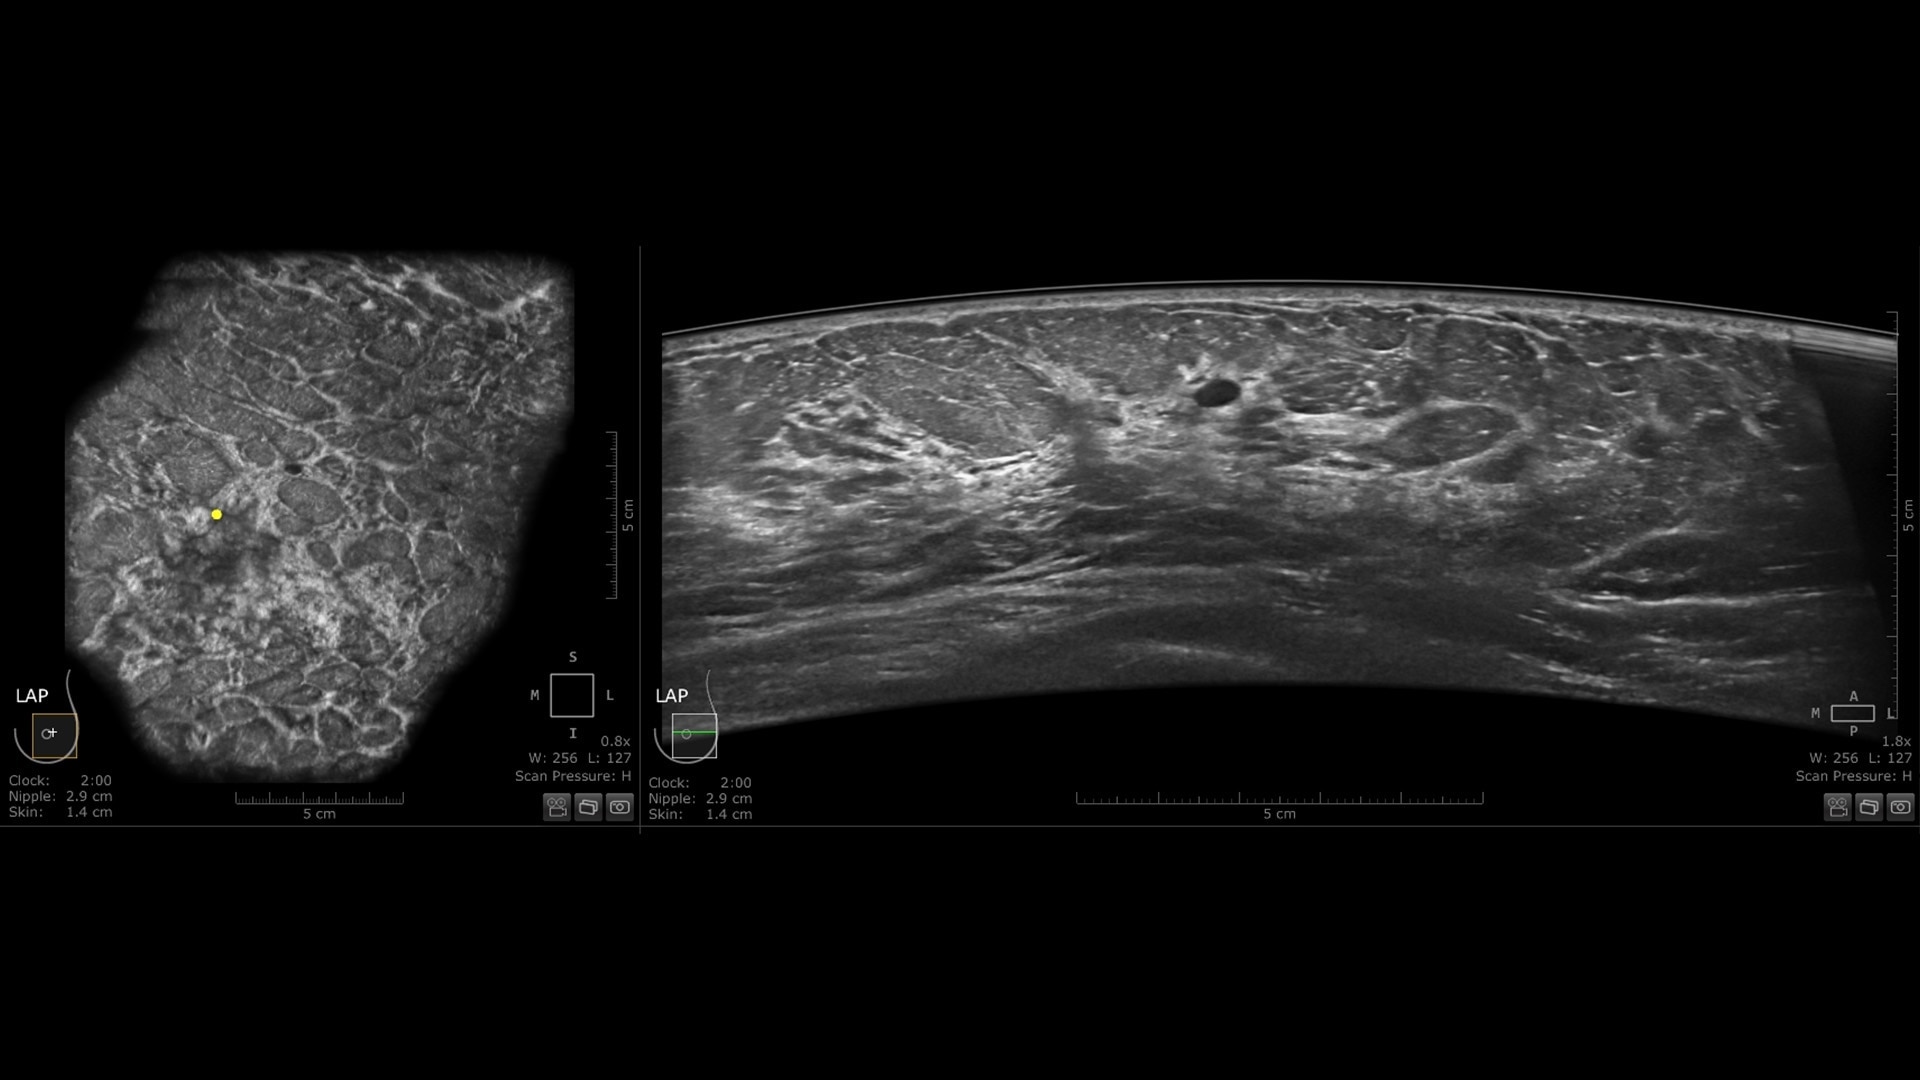

Productivity powered by AI

Boost clinical confidence and efficiency with AI-driven scanning and reading